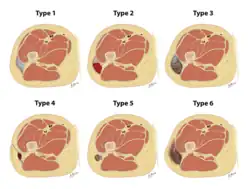

The Mellado-Bencardino classification can be used to describe a Morel-Lavallée lesion based on its MRI.[5] The classification categorizes the lesions into types.[8] The classification has six stages listed as Type I to Type VI.[5] The types do not align with specific treatments or outcomes.[4][8] The stages are based on multiple factors that can be observed on the lesion's MRI.[5] These factors include the following: the shape of the lesion, specific MRI features, and whether a capsule is present.[5][8]